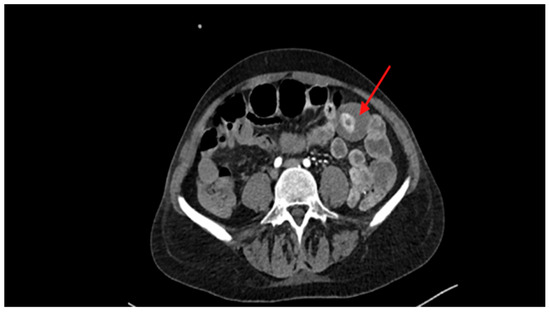

| Day 0—H20:45 | CT scan | Hyperdense intraluminal lesion in the small intestine, suspicious of bleeding lipoma. |

| Day +1—H00:00 | Clinical evolution | Persistent anemia and onset of acute obstructive abdominal condition. |